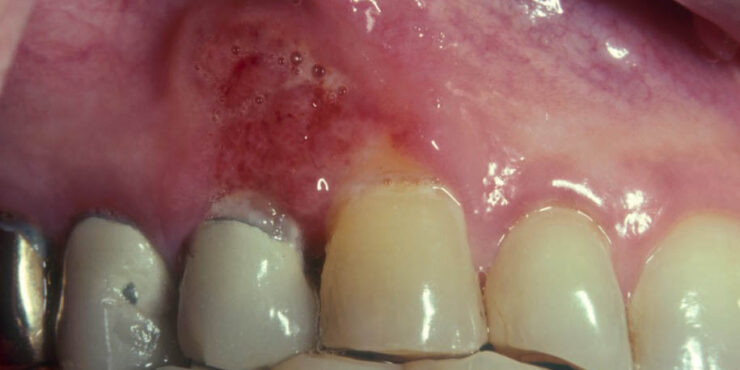

Hidradenoma = الغدوم عرقي HIDRADENOMA Epidemiology. Hidradenoma (eccrine acrospiroma) presents mainly in adults, primarily in women. Clinical Findings. Hidradenoma presents as a slowly growing, firm, solitary, smooth-surfaced, usually bluish-red, movable dermal and/or subcutaneous papule or nodule. Lesions are located mostly on the scalp, face, trunk, and abdomen, and, occasionally, on the extremities . Unusual […]